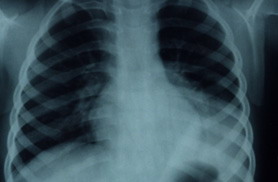

肺炎黴漿菌的感染,最常見的是「肺炎」,表現以「非典型肺炎」方式與典型細菌型肺炎高燒、咳嗽不盡相同。約四分之三肺炎黴漿菌肺炎的患兒呼吸音在聽診時會有異常,另有少部分病兒,雖然聽診是正常的,但胸部x光卻異常。胸部X光的變化並沒有一定的表現,且有時候和臨床症狀不相吻合。 例如,有的病兒看起來滿輕鬆的,但 X光卻顯示出肺炎程度厲害:有些患兒做聽診等檢查時,覺得肺炎應該很嚴重, X光照起來卻不如想像中那麼糟糕。

黴漿菌性肺炎合併左下肺肺積水

三歲幼兒以高燒不退,嘔吐厲害,輕微咳嗽表現,所照x光。